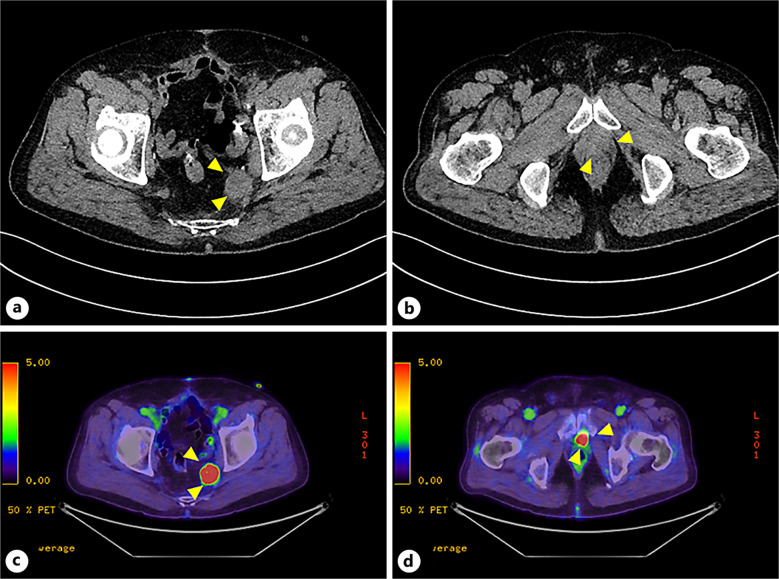

Case presentation: We report a patient with metastatic urothelial carcinoma who experienced multiple AEs associated with diabetic ketoacidosis (DKA) during EV treatment. The onset of DKA during EV treatment has been reported to be associated with poor prognosis. Although strict management was required in the intensive care unit, we were able to save the patient's life.